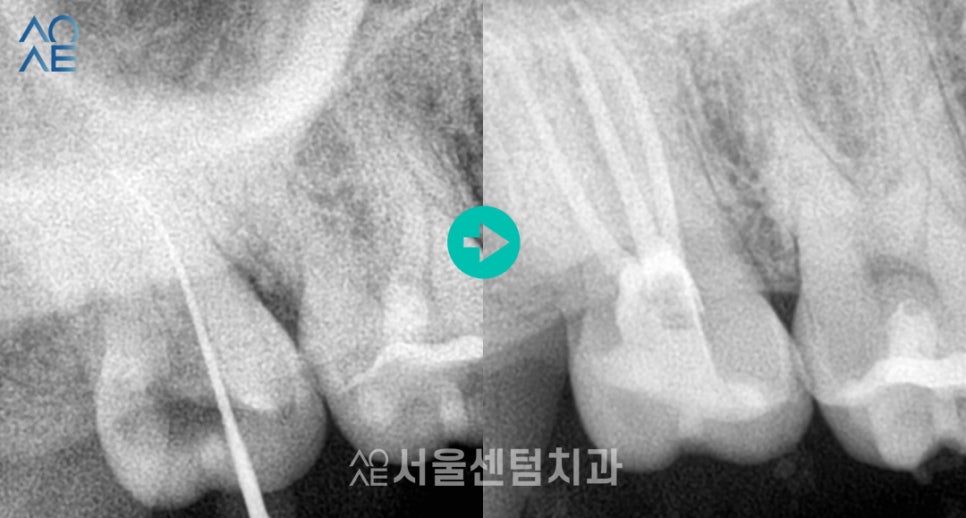

- 신경치료 시작

이미 충치가 많이 진행된 상태로

치아의 절반 이상이 치료가 필요했습니다.

여러번 내원하셔서 꾸준히 신경치료를 진행했고

약 2개월 정도 소요됐습니다.

제일 먼저 신경치료하기로 한

오른쪽 위쪽부터 발치하고

나머지는 순차적으로 진행했습니다.

전/후 비교 이미지를 보시면

깔끔하게 잘 마무리 된 모습을 확인할 수 있습니다.